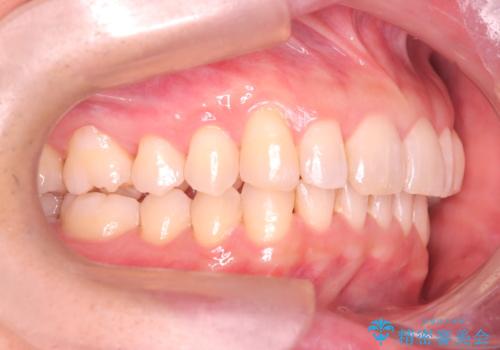

【インザライン】前歯の凸凹を治したい

- 前歯の凸凹を主訴に来院されました。

下顎位が右方に変異しており、外科矯正も提案しましたが患者様は希望されず、インビザラインにて治療を完了しております。

叢生のスペースを確保するために、臼歯部の遠心移動を行っています。

今回の治療計画は上顎の正中を顔と揃えることを優先しています。